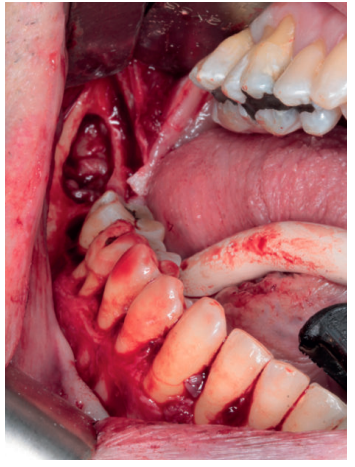

A nivel local, se anestesiaron los nervios alveolar inferior y bucal mediante articaina 40mg/ml con 0.01 mg/ml de epinefrina (Ultracain® , España). Se realizó una incisión intrasulcular a espesor total con una descarga distal alta en la rama mandibular que se extendió hasta distal del canino inferior izquierdo sin necesidad de realizar una descarga en este punto. Se despegó el colgajo con la ayuda de un periostotomo para poder acceder a la superficie ósea. Con pieza de mano y fresa redonda de carburo de tugsteno se realizaron tres cavidades equidistantes: la primera a la altura del trígono retromolar (Figura 5), la segunda apical a los premolares inferiores derechos y la tercera mesio-apical al canino inferior derecho. Dichos accesos permitieron abordar y despegar toda la lesión en su extensión para posteriormente poder traccionar de ella a través de la cavidad media (Figuras 6 y 7). La cavidad posterior sirvió también para realizar la exodoncia del cordal (Figura 8). Tras la eliminación del quiste se llevó a cabo un legrado minucioso de la cavidad remanente y se limpió con agua oxigenada. A continuación, se colocó la mini placa con una extensión desde la rama mandibular hasta mesial de la cavidad media. Por último, se reposicionó el colgajo y se suturó de forma hermética mediante una sutura poliamida recubierta no reabsorbible de 4/0 Supramid (Aragó® ) (Figura 9). La muestra obtenida se conservó en formaldehido al 10% y se envió al anatomopatólogo, el cual confirmó el diagnóstico de quiste dentígero sin displasia celular (Figuras 10 y 11).